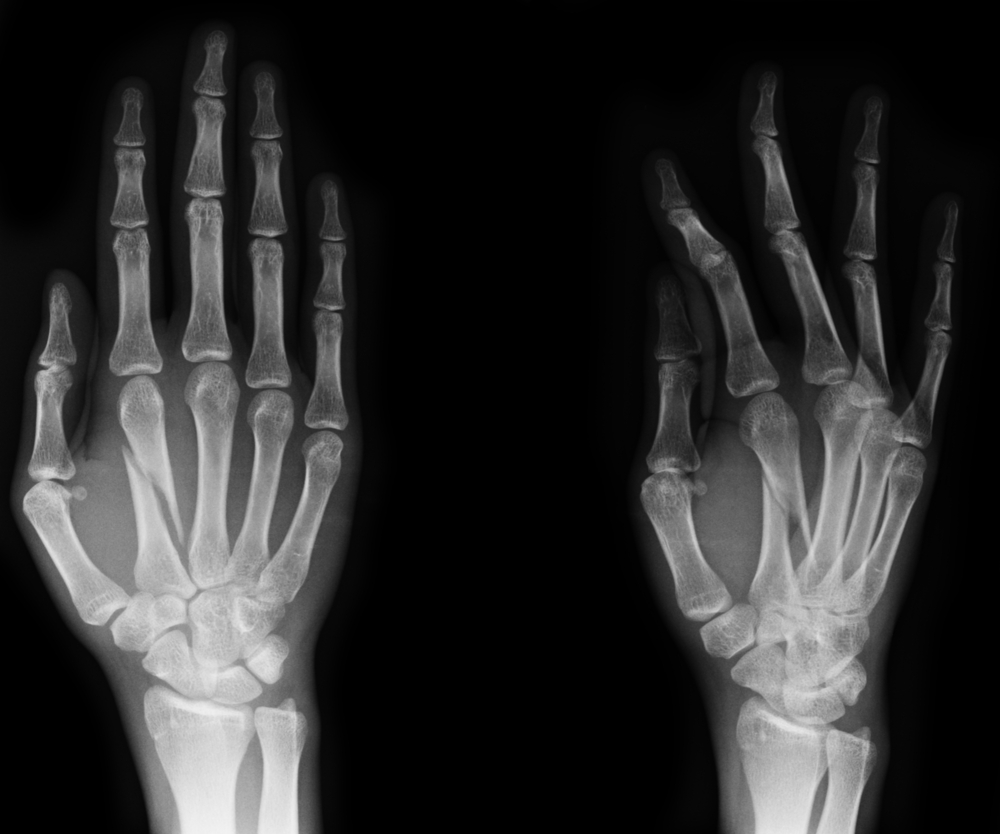

כירורגיית כף יד היא התמחות על באורתופדיה העוסקת באבחון וטיפול בגפיים העליונות – המרפק, האמה, שורש כף היד וכף היד עצמה. כירורג כף יד מטפל בבעיות שונות ומגוונות – החל ממצבים מולדים, עבור בטראומות, שברים ופגיעות ברקמות הרכות וכלה בבעיות הקשורות בהתבגרות, כמו שחיקת מפרק שורש כף היד.

בעיות בכפות הידיים שכיחות מאוד ומהוות חלק ניכר מכלל הפציעות האורתופדיות. למרות שקיים טווח רחב של מצבים שעלולים להתפתח בגפיים העליונות, כמה מהם שכיחים במיוחד.

שברים יכולים להתפתח בכל אחת מעצמות הגפה העליונה, אך הם שכיחים יותר בשורש כף היד, ברדיוס הדיסטלי (מצב שכיח בילדים ומבוגרים כאחד), בעצמות הפלנגיות באצבעות ובמרפק.